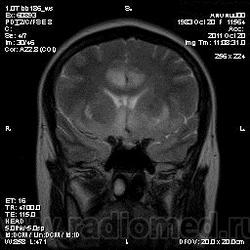

Эта же пациентка... Июль 2011 года....

В анамнезе есть зацепки на энцефалит?Мне ни разу не встречался, поэтому умничать не буду.

А здесь вариант Арнольда-Киари+ платибазия к тому же (?)

мне кажется больше похоже на диффузную глиальную опухоль. Для герпетического нехарактерна локализация и характер контрастирования. Хотя конечно нет правил без исключений..

Евгений Второй, а медиобазальные отделы височных долей - по-моему излюбленная локализация герпетических энцефалитов... Да мне кажется, что серое и белое вещество в равной степени вовлечено в процесс...

Арнольда-Киари можно указать, но вы же понимаете, что он меркнет на фоне основной патологии....

а медиобазальные отделы височных долей - по-моему излюбленная локализация герпетических энцефалитов..

Абсолютно согласен, просто у меня не все картинки раньше загрузились и показалось, что все изменения в лобных долях и базальных ядрах. Снимаю свои возражения.